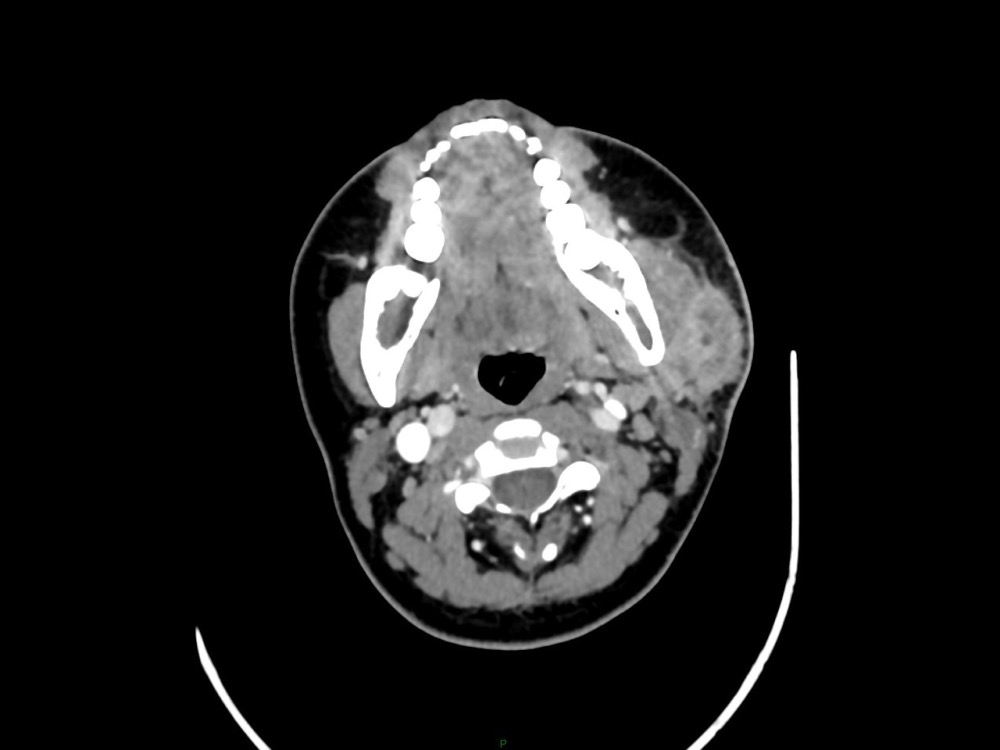

Arsovic / Perrot / Miquel 18/05/2022